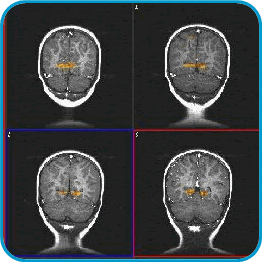

Estas imágenes, por ejemplo, son de un niño de 2 anos de edad. Se llaman cortes coronales; en ellos la cabeza se ve en la parte superior y el cuello en la parte inferior. En su interior se ven los dos hemisferios cerebrales y debajo de ellos el cerebelo. El paciente fue sedado para someterse a un procedimiento regular, después del cual, se mostraron luces intermitentes por espacio de 3 minutos. La corteza visual, situada en los lóbulos occipitales, muestra activación representada en colores rojo y amarillo.

Se han obtenido también imágenes de activación en ninos sedados con voz materna, o estímulo sensitivo de la piel (frotando la mano, por ejemplo).